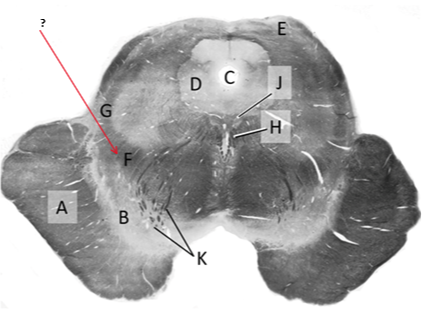

Name this and state its function.

Tectum.

Name this and its divisions+ function?

Substantia nigra.

Cerebral aqueduct.

Crus cerebri.

Medial Lemniscus.

Name this, what is it and state its function.

Lateral lemniscus.

Name this, state its function[2 marks] and how it goes about its function[4 marks].

Medial longitudinal lemniscus.

How?

Oculomotor nucleus.

Name this, state its function[3 marks] and cells involved contributing to function.

Periaqueductal grey.

Root fibres of Oculomotor nerves(CN III).